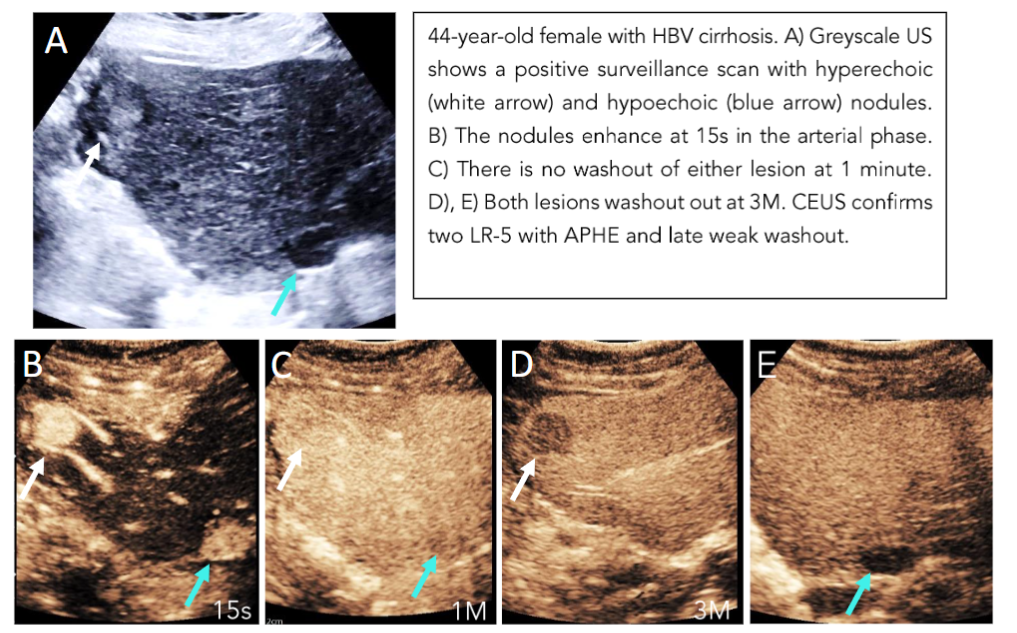

Any new nodule suspicious for HCC on greyscale US based on the LI-RADS US necessitates further multiphase contrast enhanced imaging with either MR, CT, or CEUS. HCC presents with a characteristic hemodynamic enhancement pattern of arterial phase hyperenhancement (APHE) and late mild washout in the delayed phases(15,16). Beyond creating a standardized reporting system, the LI-RADS framework is an accurate probabilistic model with the objective of providing a non-invasive means of specifically diagnosing HCC. Through a five-category classification system, it grades observed lesions using specific criteria to be “definitely benign” (LI-RADS 1) to “definitely HCC” (LI-RADS 5)(16). This results in a clear reporting system with high inter-observer reliability for the clinical team to base their management decisions on. For example, the designation of LI-RADS 5 given to a nodule greater than 1 cm with APHE and late and weak washout does not require a biopsy for a definite diagnosis (Figure 1). There are two time points that we keep in mind when looking for washout relative to time zero, which is when the microbubble contrast is flushed with normal saline. Any washout that occurs prior to 1 minute is considered early or rapid and consistent with non-hepatocellular malignancies. Washout that is marked and occurs by 2 minutes, is also indicative of a malignant non-HCC lesion. Additionally, care needs to be taken when interpreting APHE on CT and MRI in cirrhotic livers because they may represent pseudolesions such as nontumorous arterioportal shunts (Figure 2)(19).

Figure 1: Positive Surveillance scan